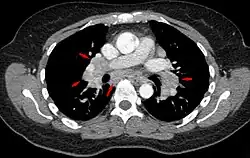

-

Hilar adenopathy especially on the person's left (AP CXR) -

Hilar adenopathy especially on the person's left (lateral CXR) -

Hilar adenopathy especially on the person's left (coronal CT) -

Hilar adenopathy especially on the person's left (transverse CT)